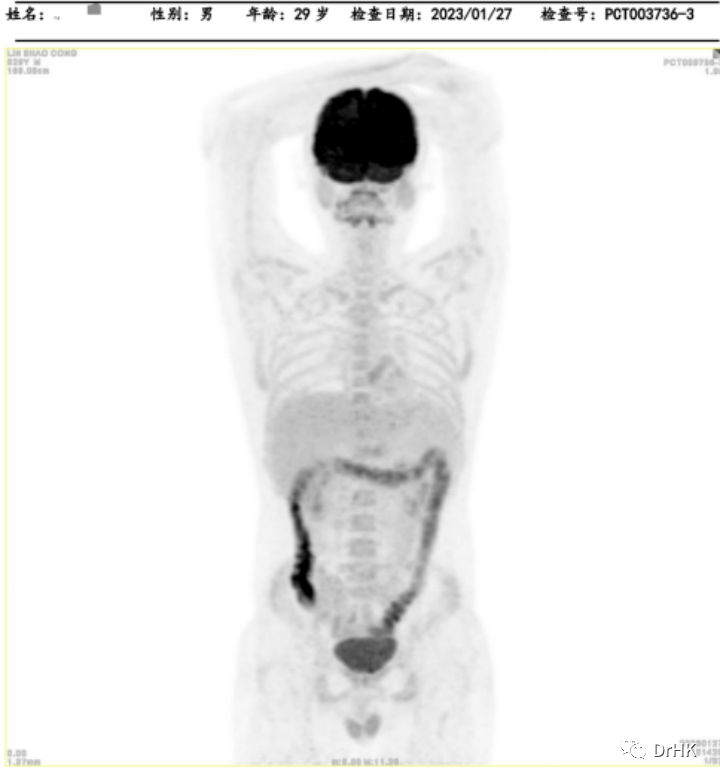

PET-CT:Deauville 评分 5 分。(1) 肝脏累及,大小约 3.2*2.6*3.7 cm,最大 SUV 值 22.4; (2) 脑部:右侧颞叶深部、基底节区稍低密度灶,结合 MRI 图像,考虑淋巴瘤累及;(3) 全身多发骨(双侧肩胛骨、锁骨、肋骨、胸骨、骨盆骨、脊椎骨)多发骨质吸收、破坏改变,部分区域骨质密度增高,以左侧髂骨为著;(4) 左侧臀大肌,范围约 1.2*1.6*1.5 cm,最大 SUV 12.4。

随后患者定期随访,分别于移植后半年、一年完善影像学评估。PET 如下图所示: